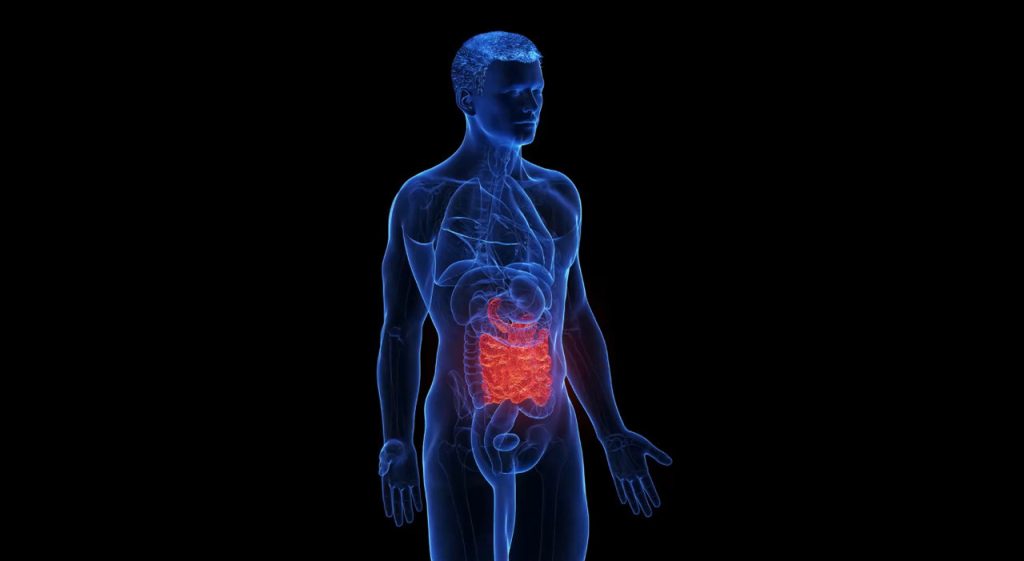

Il diabete di tipo 1, una malattia autoimmune che comporta la distruzione delle cellule beta del pancreas responsabili della produzione di insulina, interessa in Italia circa 300.000 individui. Di questi, una buona metà è di età pediatrica. La celiachia, anch’essa autoimmune, presenta sintomi diversi, ma coinvolge l’intolleranza al glutine, portando alla produzione di anticorpi contro la transglutaminasi tissutale.

Le due malattie non sono solo statisticamente sovrapposte; condividono anche una base genetica. In effetti, diversi studi hanno dimostrato che i bambini affetti da diabete di tipo 1 hanno una maggiore probabilità di sviluppare anche la celiachia e viceversa.